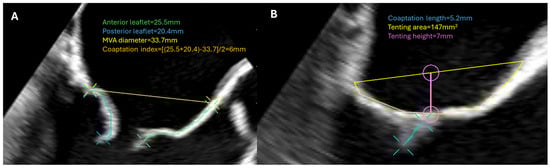

| MV repair | Describe MR mechanism Measure leaflet length Measure annulus size Estimate MR severity | Ensure sufficient MR reduction No flail part Exclude iatrogenic MV stenosis |